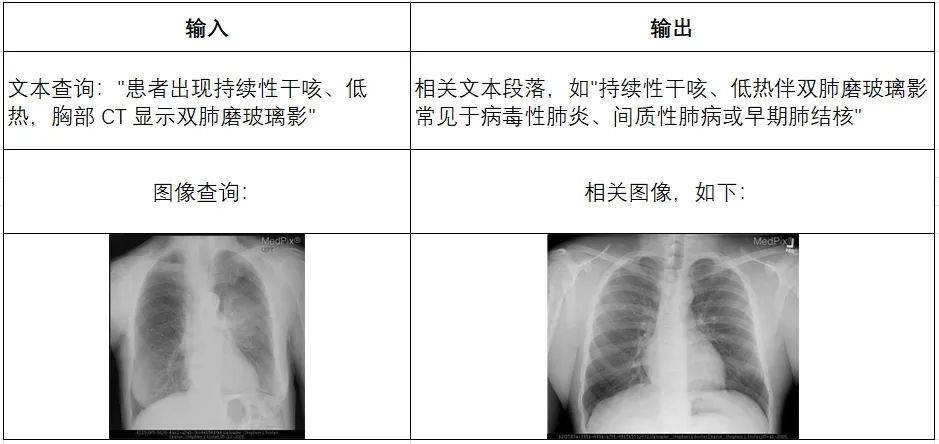

多模态检索模块:想查什么就查什么

1.基础检索

处理单一模态的查询,如文本到文本、图像到图像的匹配。例如当输入为文本查询,如“患者出现持续性干咳、低热,胸部CT显示双肺磨玻璃影”时,则会输出相关文本段落,如 “持续性干咳、低热伴双肺磨玻璃影常见于病毒性肺炎、间质性肺病或早期肺结核”;而当输入为图像查询时,如一张胸部CT图像时,则会输出胸部CT的相关图像。